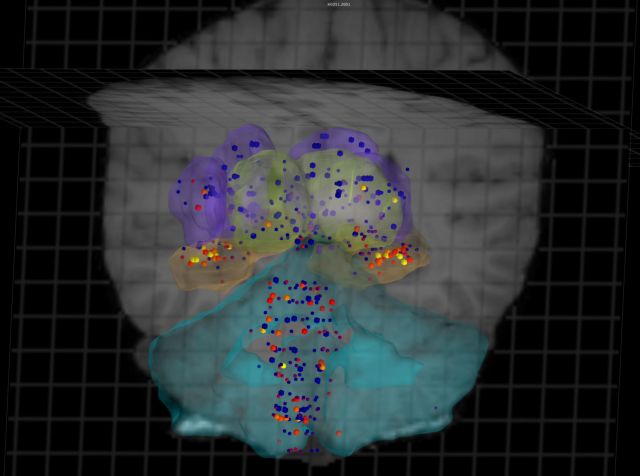

Ενας Ατλαντας που απεικονίζει τρισδιάστατα και σε υψηλή ανάλυση την έκφραση κάθε γονιδίου στις διάφορες περιοχές του ανθρώπινου εγκεφάλου ολοκληρώθηκε από διεθνή ομάδα ερευνητών. Το πραγματικά τιτάνιο έργο προσφέρει ένα σημαντικό εργαλείο για την καλύτερη μελέτη των εγκεφαλικών λειτουργιών και την ανάπτυξη θεραπειών.

Το πρόγραμμα χρειάστηκε 4,5 χρόνια για να ολοκληρωθεί (ξεκίνησε τον Μάρτιο του 2008) και χρηματοδοτήθηκε με 55 εκατ. δολάρια. Η διεθνής ομάδα των ερευνητών με επικεφαλής τον Μάικλ Χαβρίλιτς του Ινστιτούτου Επιστημών του Εγκεφάλου Allen στο Σιάτλ χρησιμοποίησε ως «βάση» για τις μελέτες της τον εγκέφαλο δυο υγιών ανδρών πραγματοποιώντας σε αυτούς 60.000 ελέγχους της έκφρασης των γονιδίων. Οι επιστήμονες μελέτησαν επίσης ένα ημισφαίριο από τον εγκέφαλο ενός τρίτου υγιούς άνδρα.

Οι ερευνητές θεωρούν ότι ο Ατλαντάς τους θα προσφέρει πολύτιμες πληροφορίες για την επίδραση που μπορεί να έχουν οι γενετικές διαταραχές στις διάφορες περιοχές καθώς και για τα λειτουργικά δίκτυα του εγκεφάλου. Ελπίζουν ότι στο μέλλον θα επιτρέψει τη σύγκριση τόσο των «φυσιολογικών» και «μη φυσιολογικών» εγκεφάλων μεταξύ τους όσο και τη σύγκριση του ανθρώπινου εγκεφάλου με εκείνους των άλλων ζώων.

Ηδη οι ειδικοί παρατήρησαν ότι τα βασικά λειτουργικά χαρακτηριστικά του ανθρώπινου εγκεφάλου διατηρούνται σταθερά από άτομο σε άτομο αλλά παρουσιάζουν κάποιες διαφορές σε σύγκριση με τον εγκέφαλο του ποντικού και του μακάκου. Ο εντοπισμός των κοινών σημείων και των αποκλίσεων στις εγκεφαλικές λειτουργίες θεωρείται πολύ σημαντικός καθώς μπορεί να προσφέρει εξηγήσεις για τη διαφορετική δράση που φαίνεται να έχουν συχνά τα φάρμακα στα διάφορα είδη.